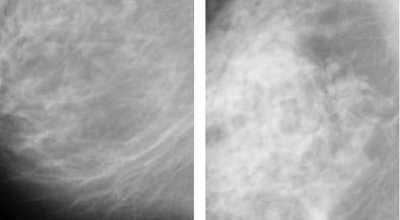

| Architectural distortion in breast tissue (seen in mammographic breast image at right) is a potential indication of malignancy that is often missed by radiologists and CAD systems alike. The distortions can be difficult to appreciate even in the enlarged view (bottom). Images courtesy of Rangaraj Rangayyan, Ph.D. |

![]() |